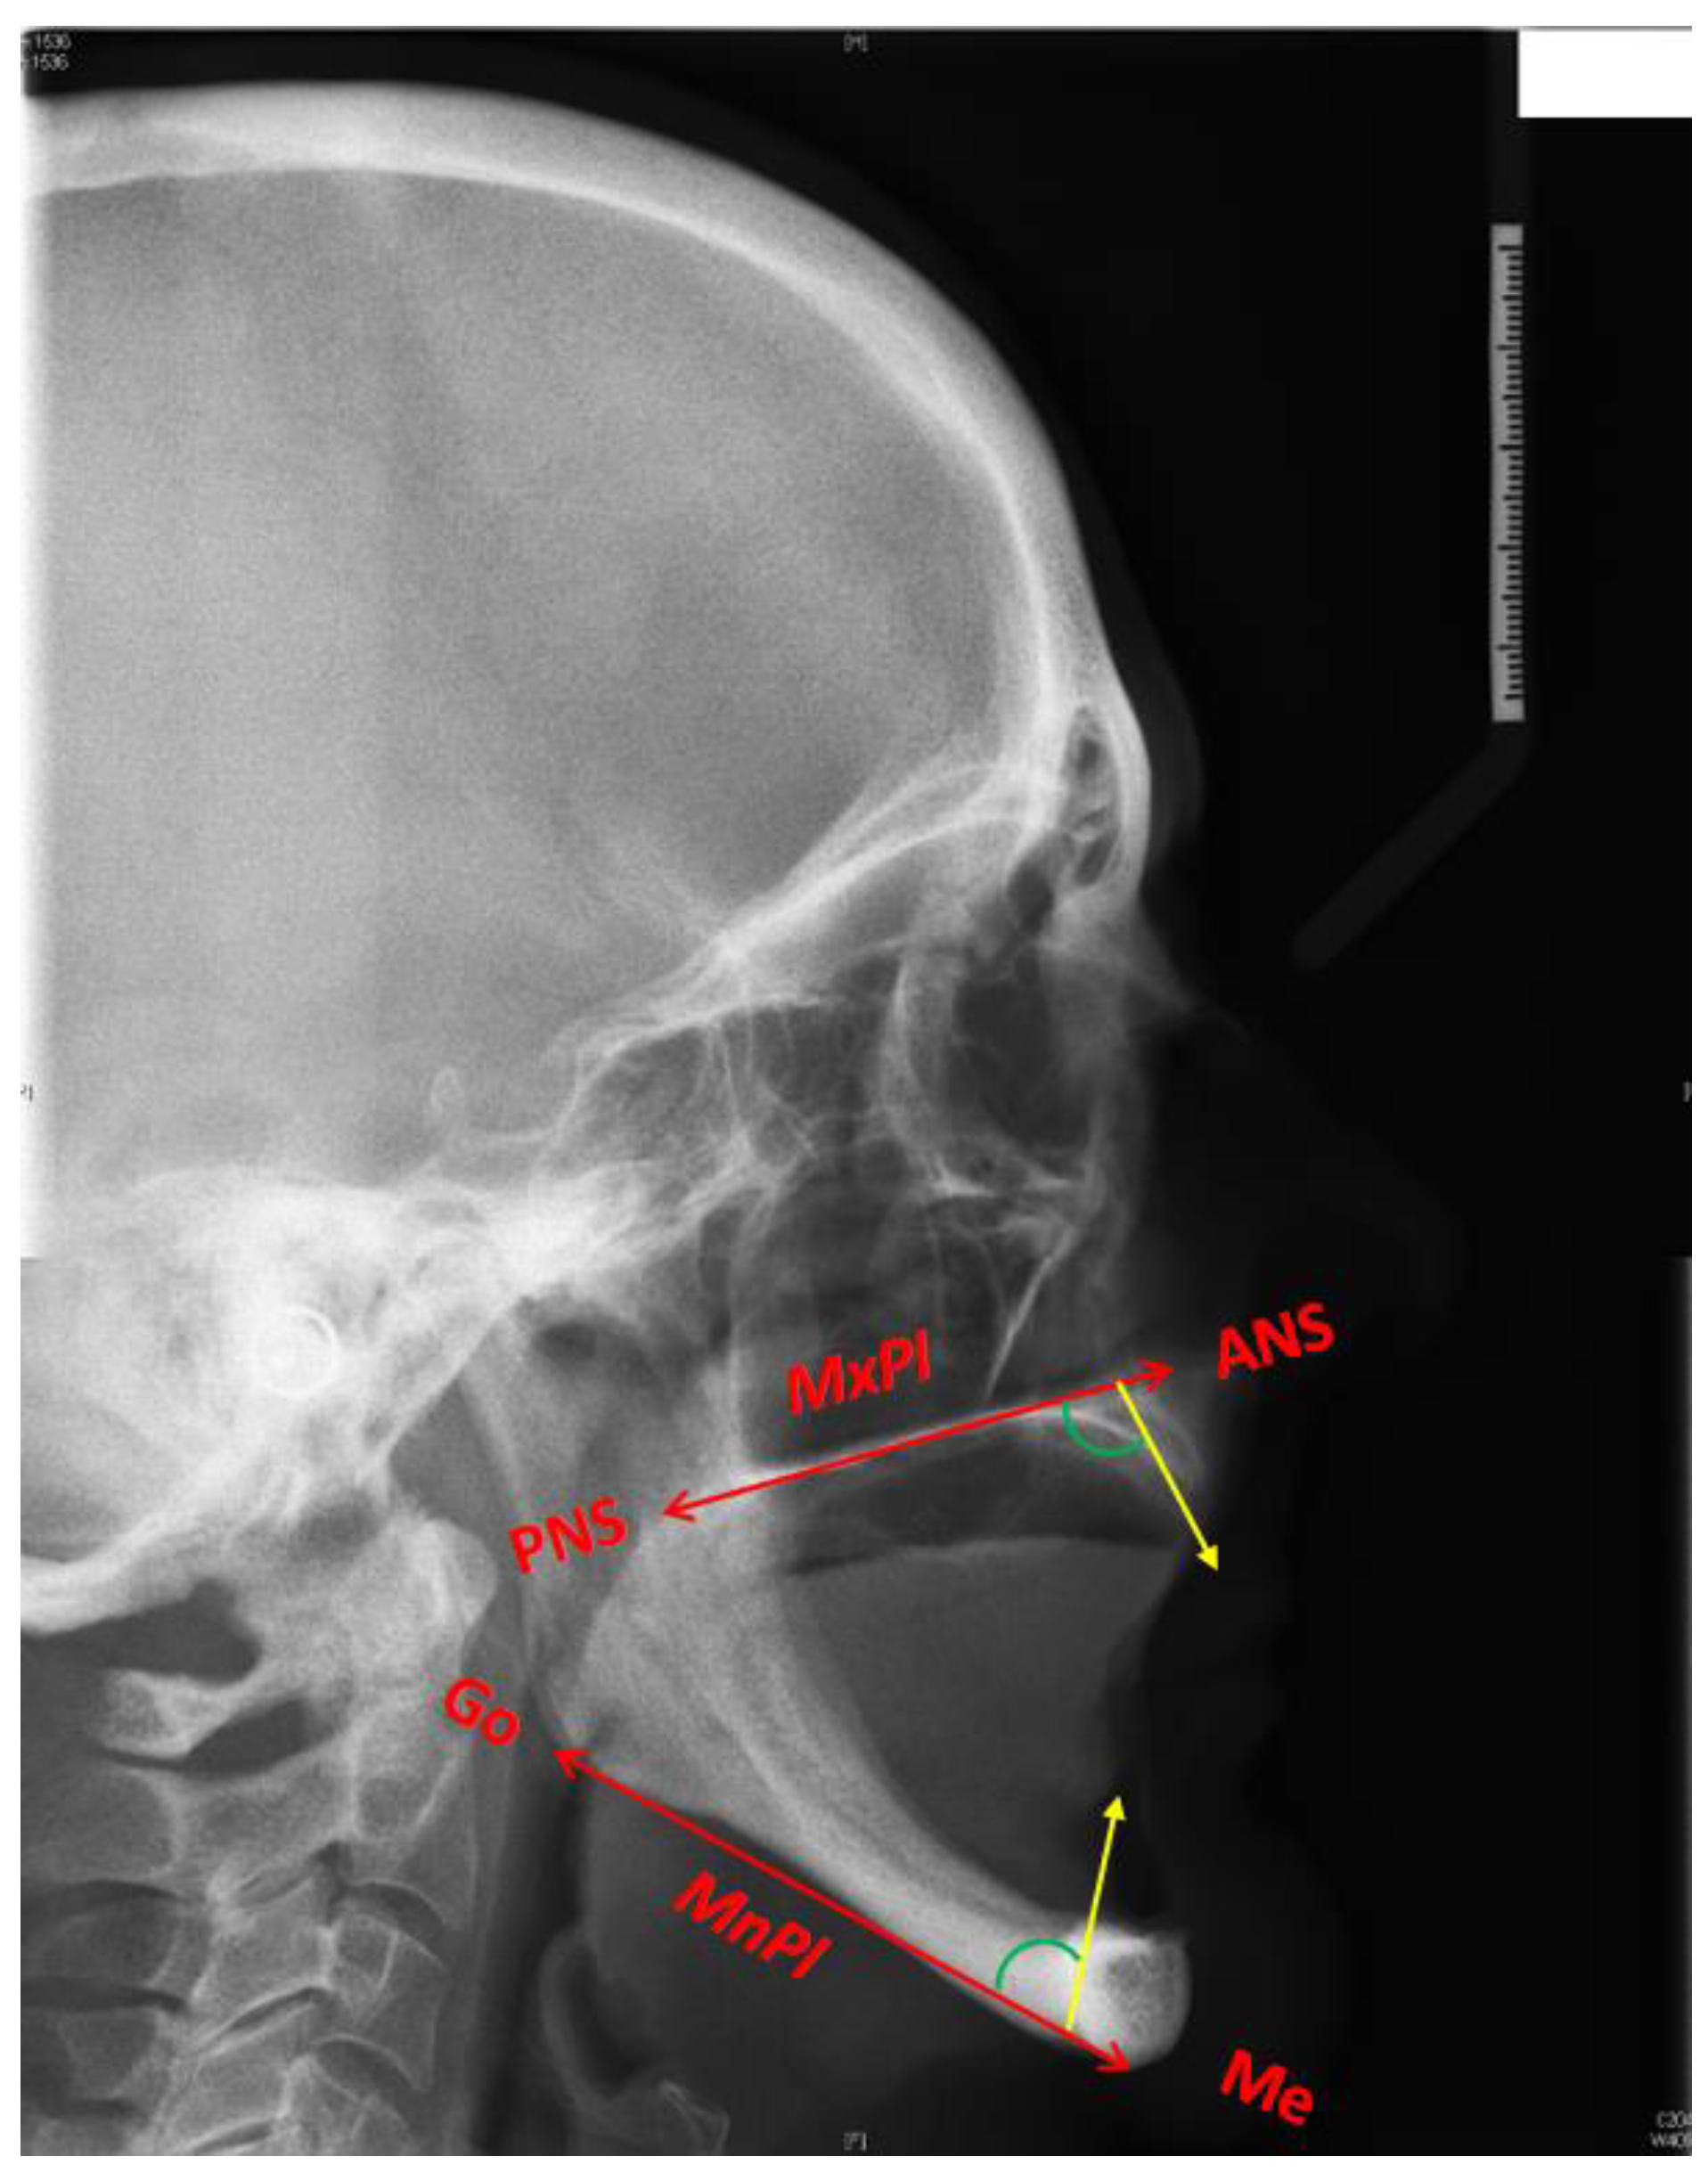

From www.semanticscholar.org

Figure 1 from The influence of bone mineral density and body mass index Jaw Bone Resorption With bone imaging technologies, your doctor can look for bone loss while you’re still in the early stages. Bone resorption is part of a complex biological process that can result in shrinkage or loss of bone. It’s essential to know the symptoms and how to get treatment. Jaw bone resorption is a severe condition that can cause many problems for. Jaw Bone Resorption.